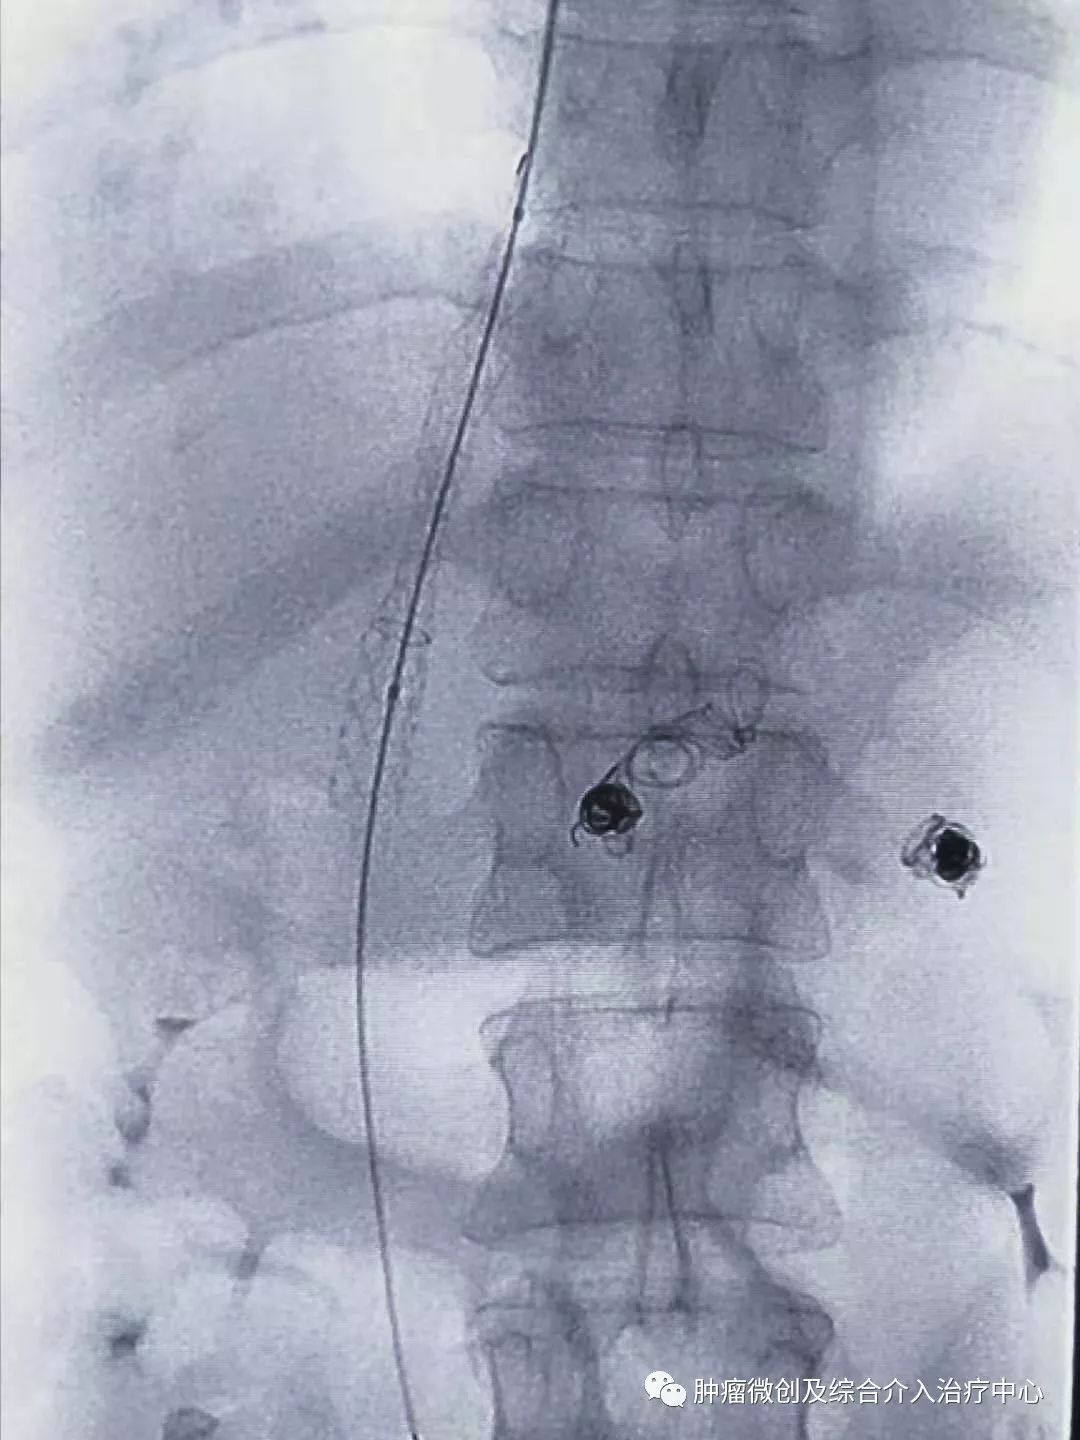

栓塞消化道出血责任血管:

球囊扩张静脉-门脉支架:达到门脉-体静脉充分分流目的